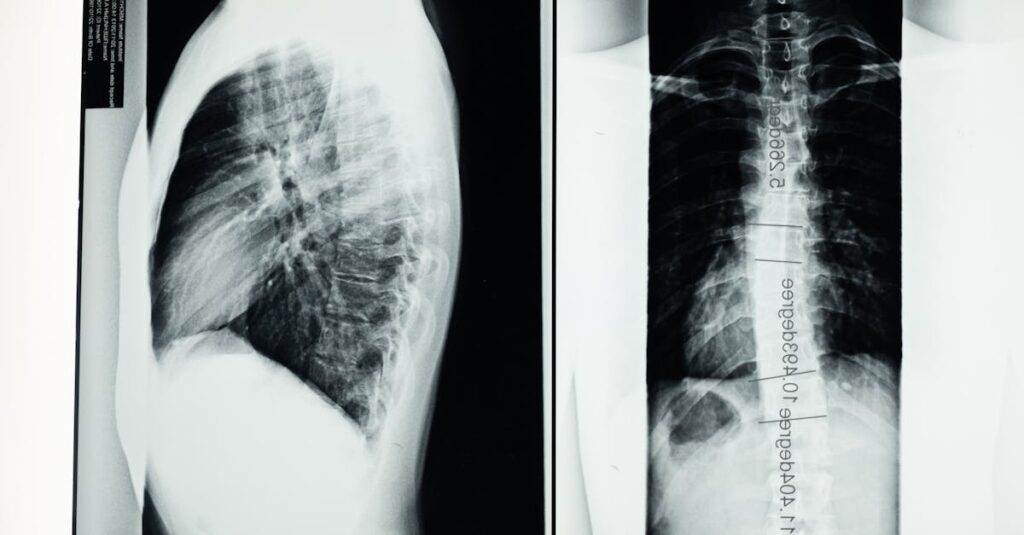

Comment diagnostiquer correctement la brachialgie?

Un examen clinique, combiné à une imagerie médicale comme une IRM, est nécessaire pour un diagnostic précis.